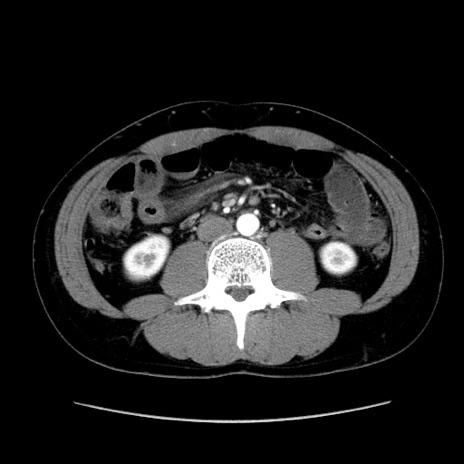

症例36(横断像)

【症例】20歳代 男性

【主訴】心窩部痛

【現病歴】今朝より上腹部痛あり。一旦軽快していたが再度出現したため救急要請。昨日夕に白身の魚を含む刺身を食べた。

【身体所見】BP 136/89mmHg、HR 74/min、BT 37.0℃、腹部:膨満、軟、心窩部に圧痛あり。反跳痛なし、筋性防御なし、腸雑音やや亢進あり。

【データ】WBC 17700、CRP 0.48